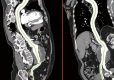

3D reconstruction obtained for pre-operative planning. The patient is a 68-year-old male and current smoker who was found to have an infrarenal AAA on screening ultrasound. AAA, abdominal aortic aneurysms.